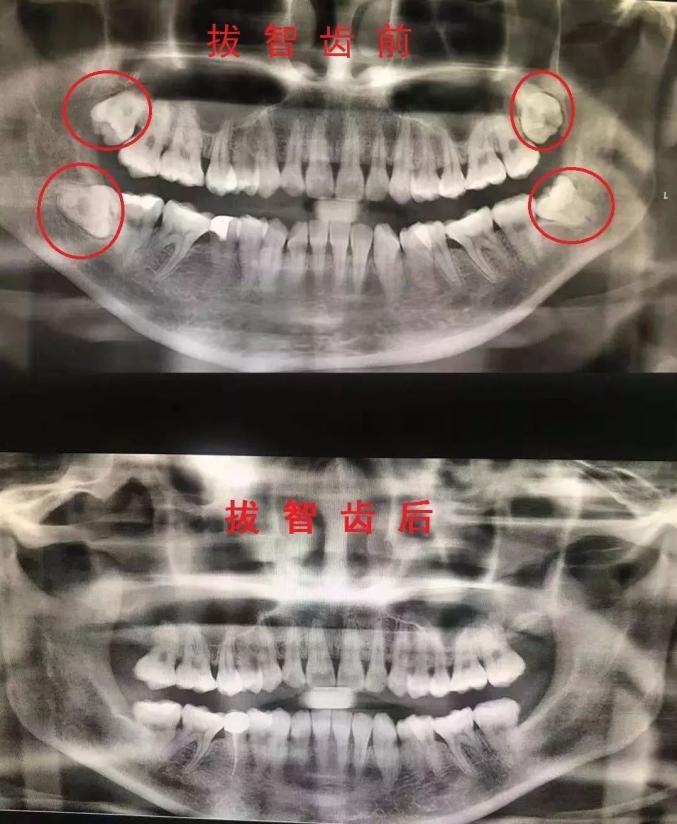

什么叫做“叛逆少年型”?看看下面的图片感受下——

看到没?

这些都是走了歪路的“叛逆少年”

关于智齿,大部分人的真实写照都是:智齿不痛就可以不拔!其实,大部分智齿都会长歪,或者发炎,遇到这种情况,建议拔掉智齿!